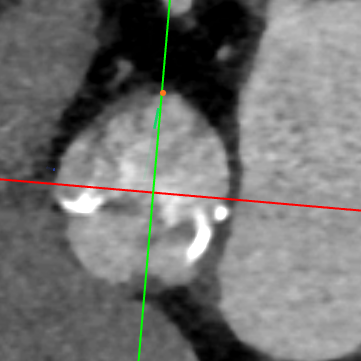

武汉协和董念国团队对该病例进行了缜密探讨,该病例为老年男性,主动脉瓣中重度狭窄,术前左室舒张功能减低。患者病例CT和心超数据显示瓣环周长:90.2mm,瓣下4mm流出道周长:97.5mm,窦部空间相对小,单纯无冠瓣瓣叶钙化,三叶瓣。左冠风险较高,缜密分析瓣叶遮盖率>50%,术中可能存在阻挡风险,需要术中球囊扩张时仔细辨认,并准备冠脉保护策略。综合评估考虑右股动脉更适宜为主入路。经过团队严谨的评估及充分的讨论,决定先行25mm球囊预扩并进一步确认冠脉风险,并准备TAV29和TAV32规格的ProStyle预装式可回收TAVR系统。

术者采用患者右侧主入路,顺利完成导丝和猪尾跨瓣等准备工作。进Landerquist超硬导丝,采用25mm球囊进行预扩,仔细评估冠脉风险后,决定对冠脉采取保护措施。根据球囊扩张情况,术中决定使用金仕生物的ProStyle预装干瓣TAV32。打开包装后,很迅速的完成了瓣膜和系统植入前的准备。输送过程系统和瓣膜轻松过弓并顺利跨瓣;开始初步释放,然后快速起搏下释放,发现位置略高后进行回收,重新定位后最终成功完成释放。反复造影发现冠脉存在阻塞风险,武汉协和团队按照风险预案在左冠植入4.0*18mm支架进行保护。术后显示左右冠脉血液灌注通畅,术后超声测量峰值流速1.45m/s,峰值压差8mmHg,几乎无瓣周漏。入路闭合顺利,无心脏及血管并发症,手术成功。